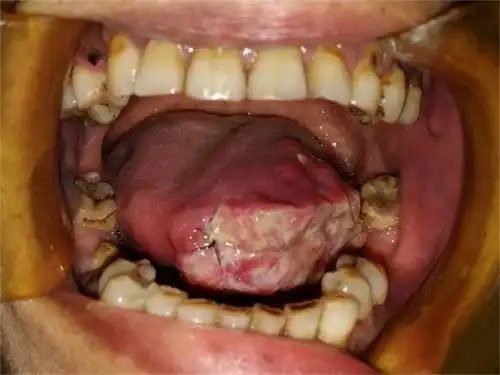

口腔癌

口腔变这样 肿瘤 2个月变5倍大

口腔癌指发生在口腔的恶性肿瘤,有舌癌,牙龈癌,腭癌,口咽癌,唇癌等,是

口腔癌的前兆 (7)